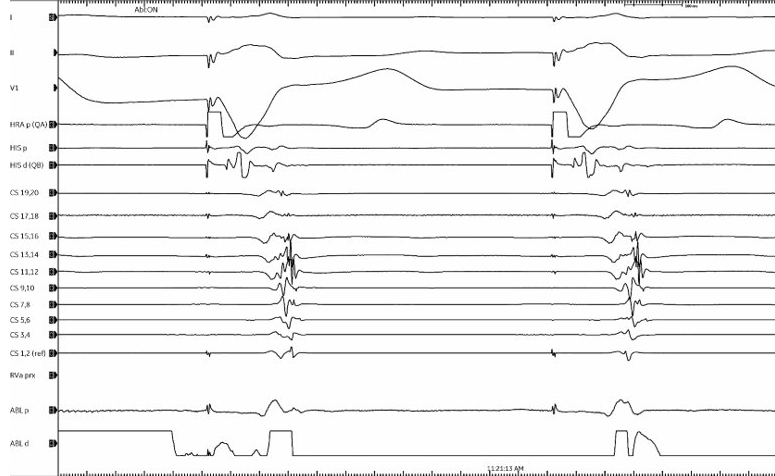

Did my first solo SVT as an attending today :) Concealed LLAP, one burn term 🔥